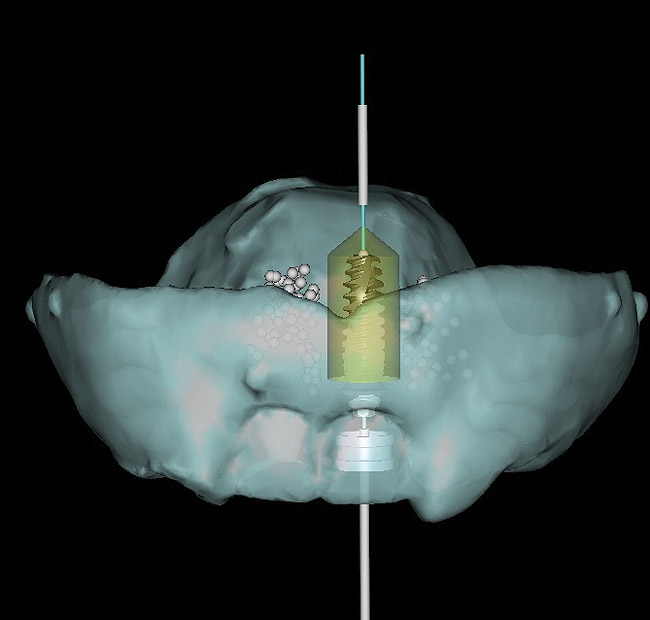

Figure 4  Dental implants virtually placed in close proximity to inferior alveolar nerve. Note green dots representing roots of adjacent teeth in surgical site.

Figure 4